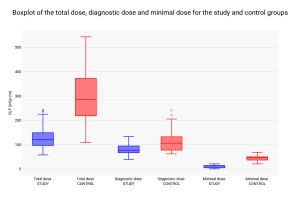

The Dose Length Product (DLP) in the study group was significantly lower than in the control group (Table 2; Figure 1).

The study group had a mean total DLP of 134.71 mGy.cm, compared to 313.13 mGy.cm in the control group. This equates to a dosage reduction of 56.97%.

The mean DLP for diagnostic acquisitions was 89.46 mGy.cm in the study group against 128.43 mGy.cm in the control group. This equates to a dosage reduction of 30.34%.

The mean DLP for minimal dose acquisitions was 9.77 mGy.cm in the study group against 44.71 mGy.cm in the control group. This equates to a dosage reduction of 78.4%.